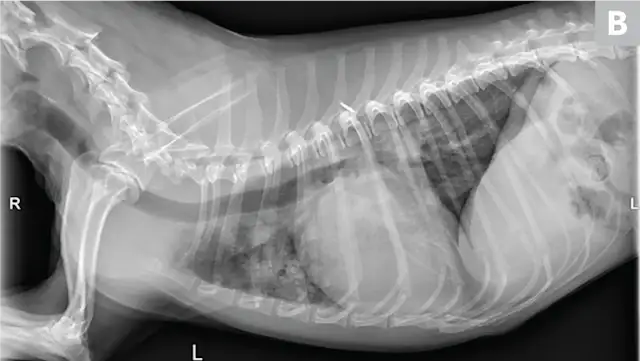

CDV should be suspected in poorly vaccinated dogs with multiorgan involvement. Dogs with CDV may have exhibited only respiratory signs before developing characteristic nonrespiratory signs.12 Radiographs may reveal a diffuse interstitial pattern (Figure 2). Diagnosis is supported by compatible clinical signs and complementary diagnostic testing (ie, real-time reverse transcription polymerase chain reaction [RT-PCR], serology, CSF pleocytosis). Conjunctival scraping and tissue-based immunohistochemistry may confirm diagnosis.

FIGURE 2

CDV pneumonia with a diffuse interstitial pattern confirmed by multisystemic signs, urine RT-PCR, and necropsy